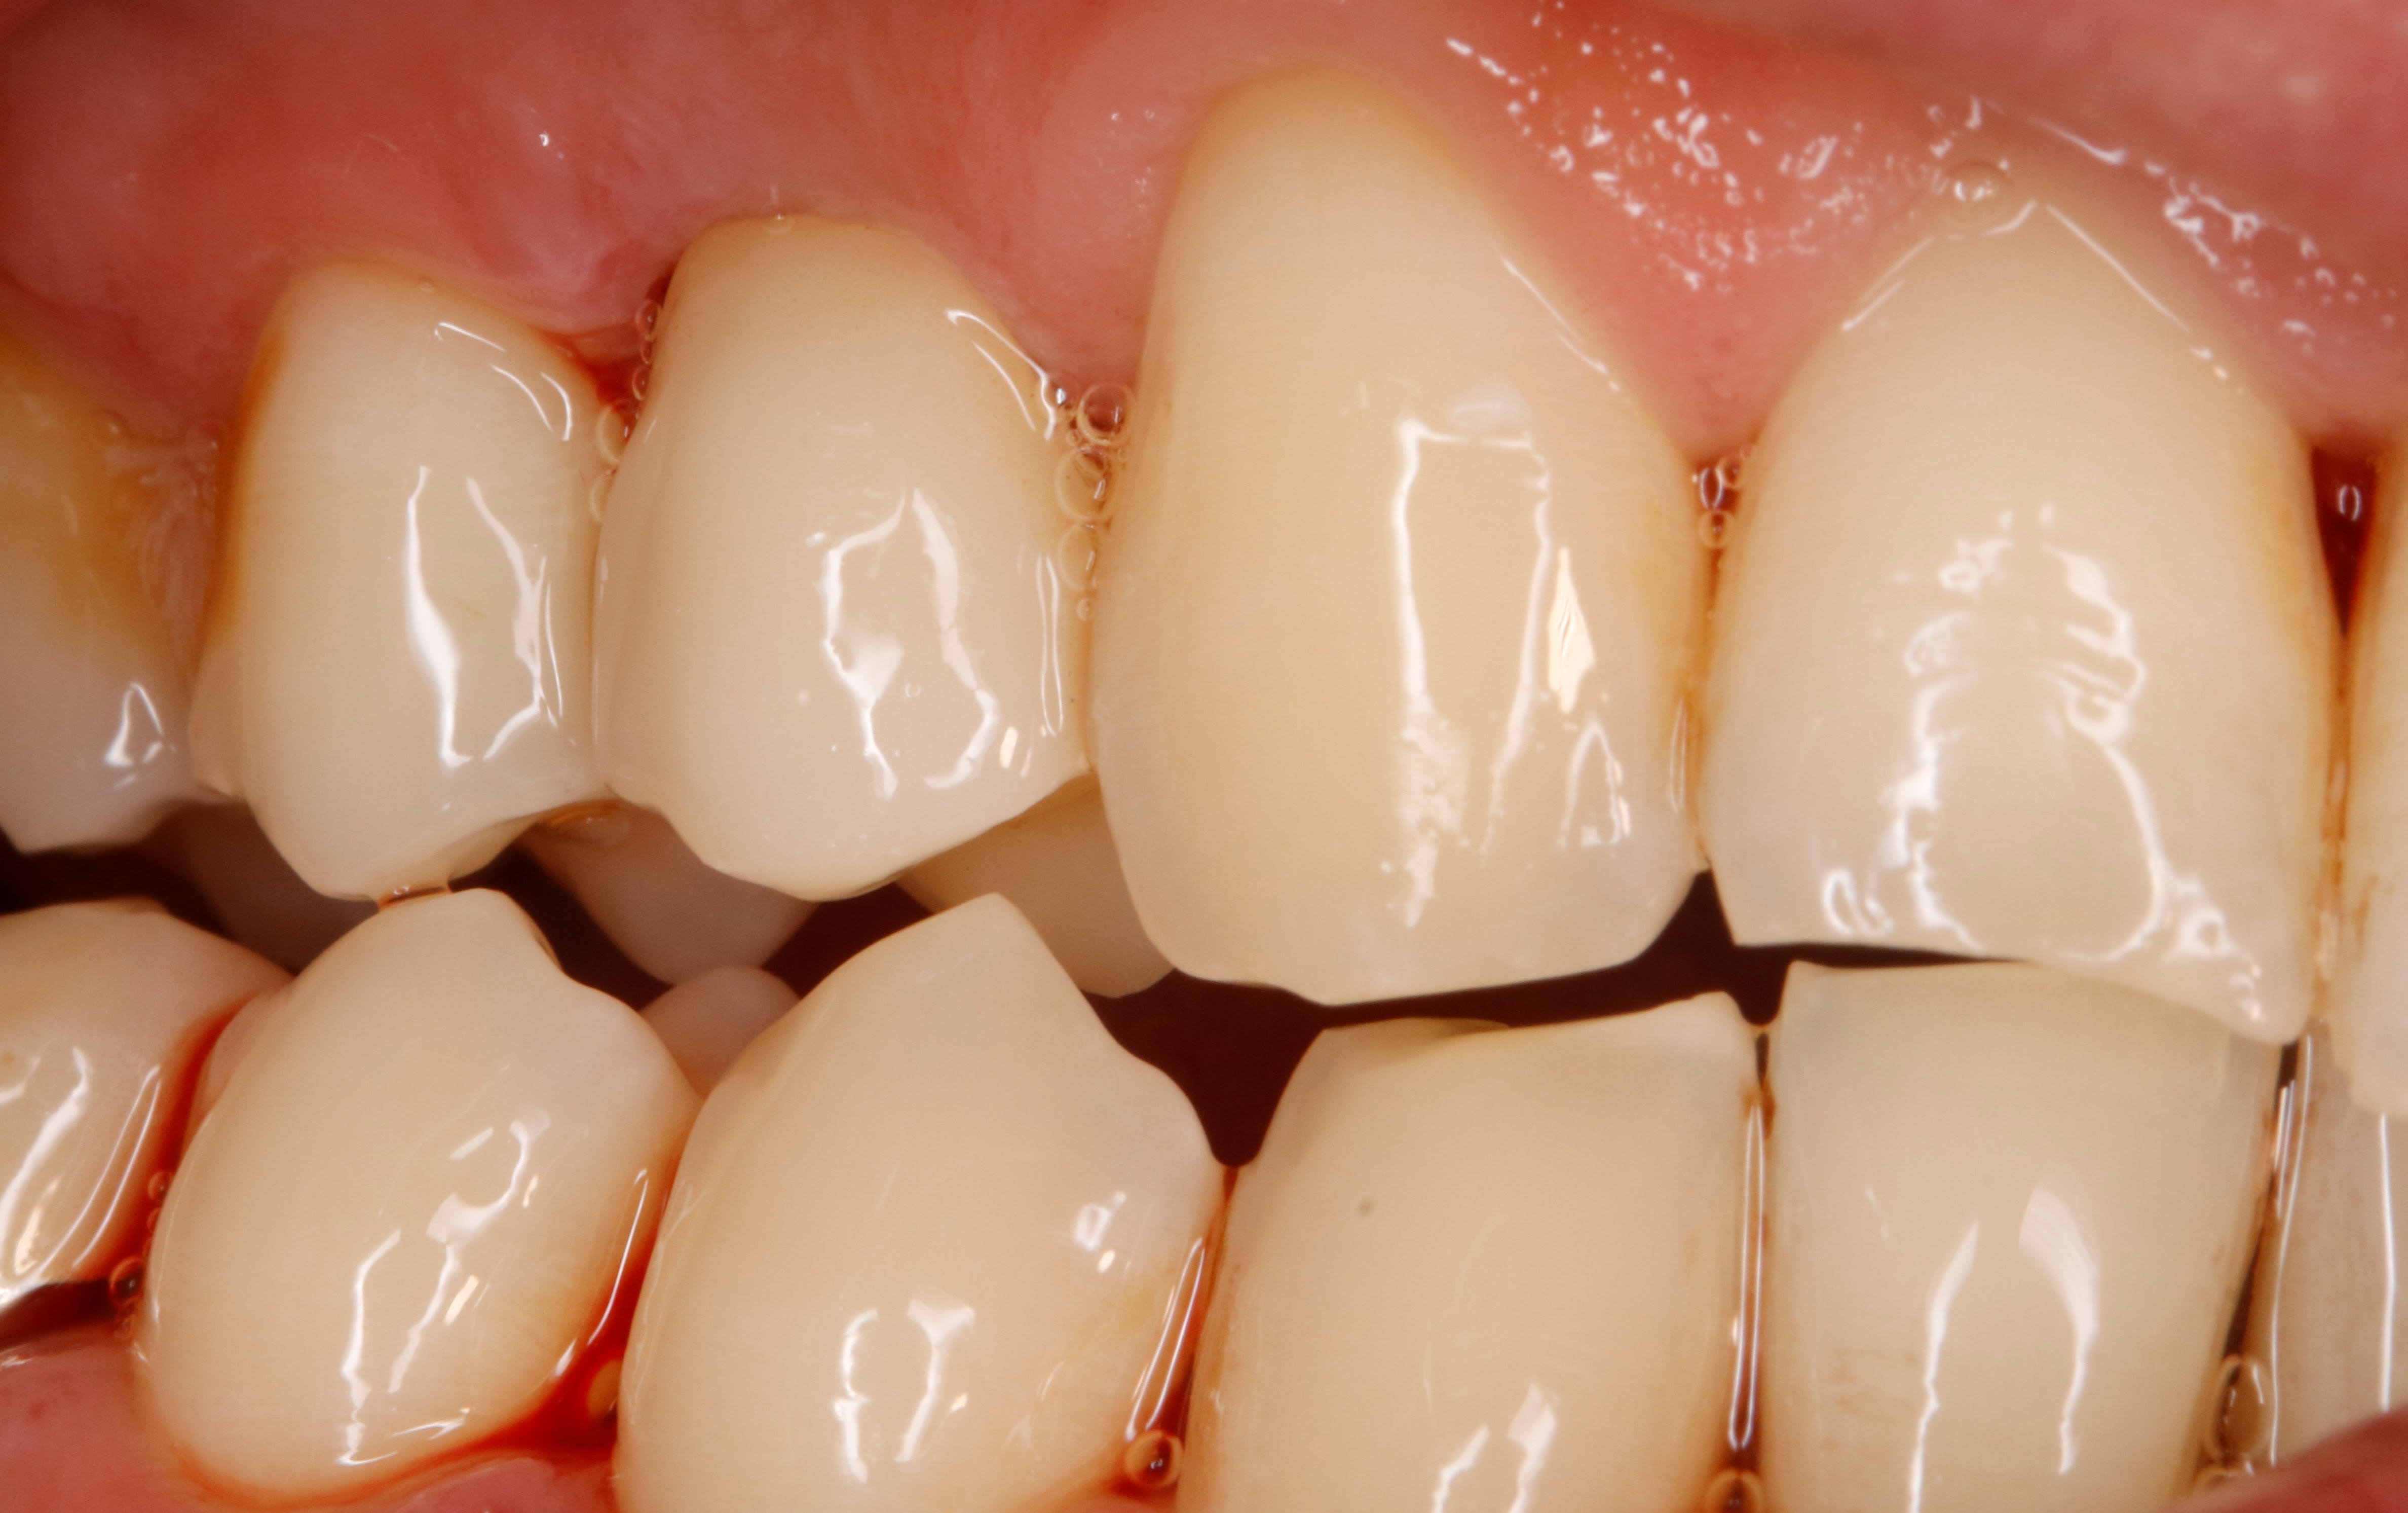

quelle belle gencive... ça doit être un vrai plaisir de travailler dans ces bouches...

lui il ressemble à la question du post , normalement il revient demain matin .

en principe , sans prov , ils n oublient pas :-)

25/04/2025 à 11h38

comme prévu il est venu , tu m étonnes :-)

j avais pris l empreinte la séance dernière et ce matin il est comme ça .